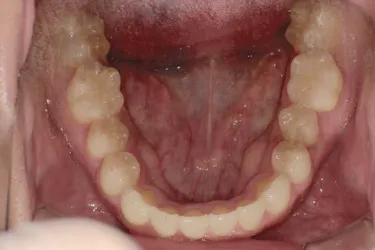

人と接する機会が多く、第一印象を大切にしたいと考え、写真写りや笑顔への自信を高めたいという思いから矯正を決意された矯正当時学生だった22歳男性の H.S.様に、スマイルモア矯正を選んだ理由を伺いました。

| 詳細情報 | |

|---|---|

| 費用 | 360,000円(税込396,000円) |

| 治療期間 | 11ヶ月 |

| 治療内容 | マウスピースを用いた歯列矯正 |

| 追加処置 | IPR |

以前よりも歯並びが改善され、人とコミュニケーションをとることに自信がつきました。 「スマイルモア」という名前の通り、笑顔に自信がついたことで今までよりも口を開けて笑う機会も増えました。 矯正期間が年単位だったのですぐに変化があったわけではないですが、綺麗な仕上がりに満足しています。